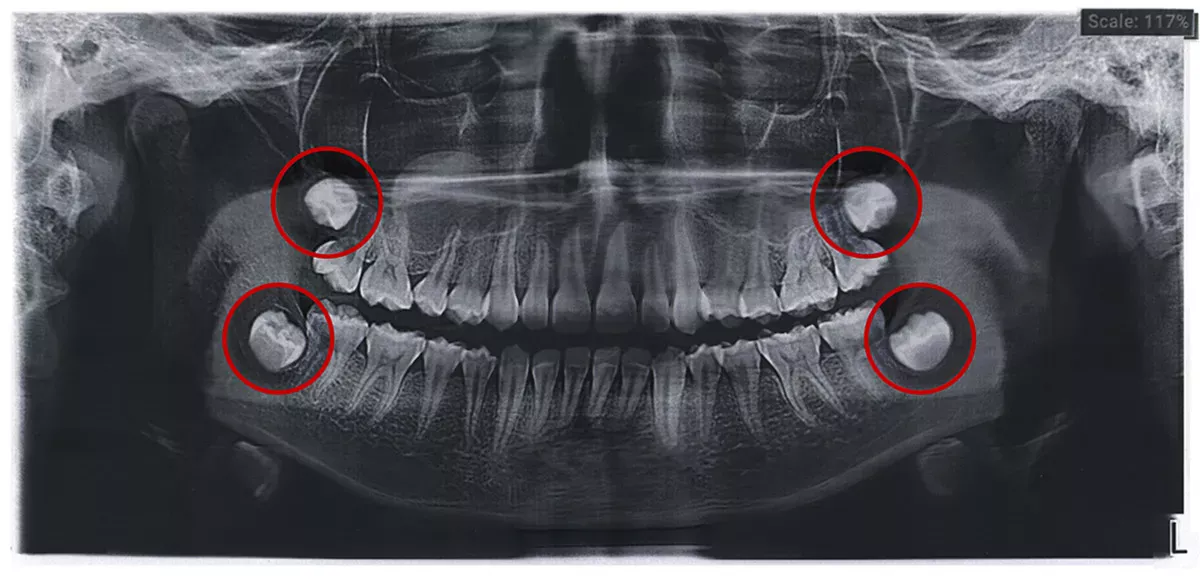

Wisdom teeth can have three to five cusps and up to five roots, which are often fused together or curved. The appearance can therefore vary greatly.

In this article you will find some pictures of wisdom teeth - both x-rays and photos of extracted teeth and graphics - to give you a good idea of what wisdom teeth look like.

Impacted wisdom teeth

If the wisdom teeth do not grow into the mouth at all, but remain in the jaw, they are referred to as "impacted wisdom teeth". People with impacted wisdom teeth often have no symptoms. However, if the wisdom tooth sits at an angle in the jaw and presses on a neighbouring tooth, it can damage the tooth. This can result in root caries, bone loss in the jaw or the teeth shifting due to the pressure.

Cysts can also form on impacted wisdom teeth, which the dentist can recognise on an X-ray. Cysts are filled with fluid and do not initially cause any pain. However, if they become inflamed, they can cause a feeling of pressure and dull pain.